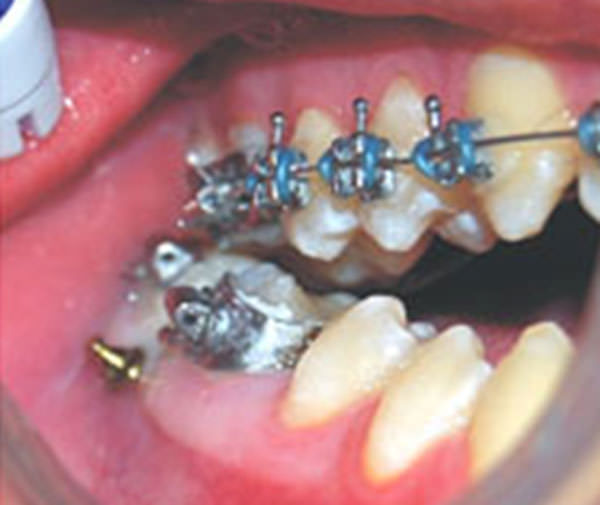

Inserción de mini-implante

Figura 8

Figura 9

Mini-implantes en el arco inferior

Figura 10

Figura 11

Este paciente ameritaba realizarle intrusión de los molares 6 y 7 de cada arco inferior y luego los 6 del arco superior. Comenzamos realizando una disyunción con Haas modificado para la corrección de la mordida cruzada posterior, permaneciendo en boca 4 meses (Figura 6). Después se utilizó los aparatos de Ortodoncia por medio de braqueado con la técnica Roth (pretorqueado) con slot 0.22 X 0.28, retroligaduras de 0.8 como medio de anclaje postero-anterior, ligas intermaxilares de 3/16 de 4 onzas y mini-implantes ortodóncicos auto-perforantes de titanio, con perfil transmucoso corto de 1mm de 1,6mm y longitud de 8,0mm, tipo de cabeza High Utility Pot™ (Figuras 7, 8, 9, 10, 11, 12, 13, 14, 15, 16 y 17).